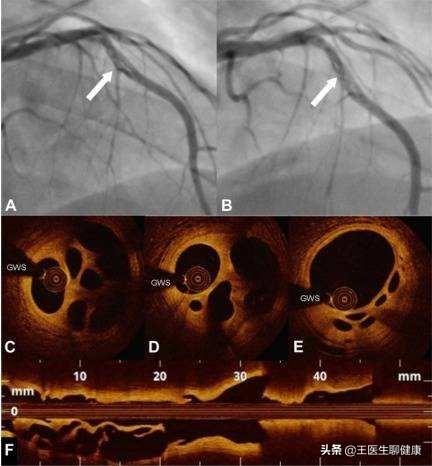

4、石灰化を伴う多枝病変:冠動脈造影の結果、左主幹+3枝病変を含む冠動脈の多枝病変が認められ、ステント治療が可能であるが、多くのステントを留置する可能性があり、石灰化病変は手術が難しく、手術時間が長く、大量の放射線が必要である。外科的バイパス手術も考えられるが、バイパス手術は回復が遅く、治療期間も長い。状況に応じて、医師が理想的なプランを提示します。

下図は左主幹部の多枝病変である。